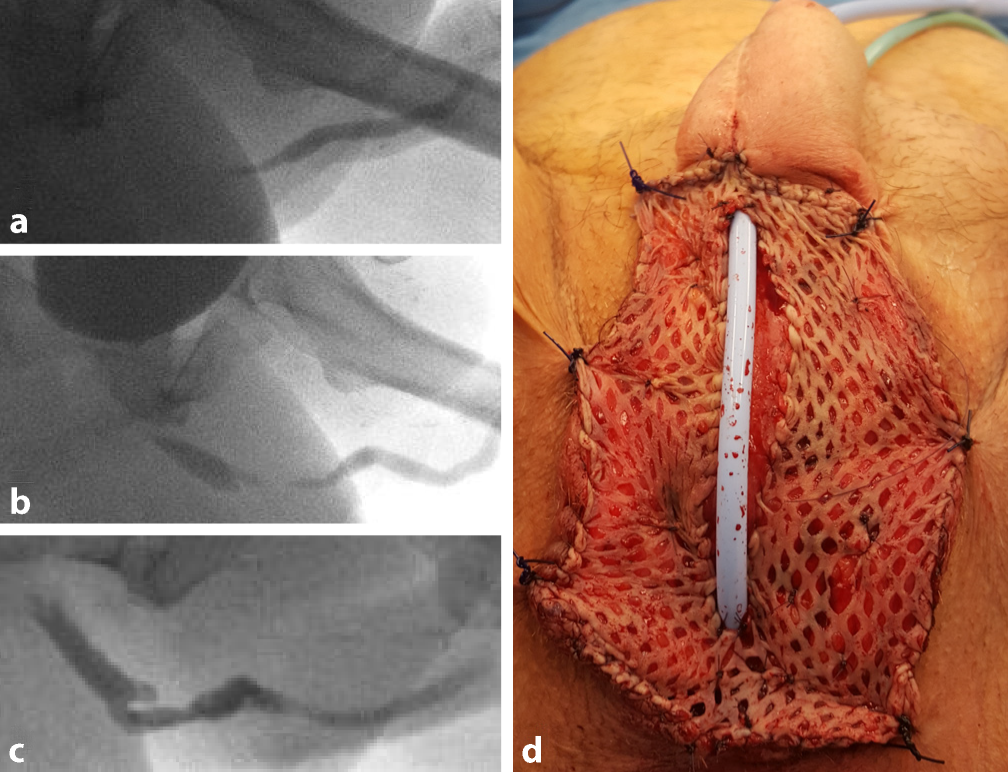

Kurzstreckige Strikturen im Anastomosenbereich zwischen Pars pendulans und Pars fixa oder auch in der Pars fixa können primär mit einer End-zu-End-Urethraplastik (Abb. 6a, b) behandelt werden. Hierbei werden das enge Segment reseziert und die verbleibenden Enden spatuliert und anastomosiert. Limitierender Faktor ist hierbei die fehlende Mobilität der Urethra insbesondere in der Pars pendulans. Alternativ kann eine Urethraplastik nach Heineke-Mikulicz (Abb. 6c, d) erfolgen, bei der die Striktur längs inzidiert und quer vernäht wird. Insbesondere die weiche und elastische Pars fixa eignet sich hierfür sehr gut. Langstreckige Strikturen der Pars pendulans, wie in Abb. 6e, f dargestellt, können primär mit Grafts oder Flaps behandelt werden. Wie beim Cismann können Vollhaut oder Mundschleimhaut als Grafts verwendet werden, mit Offenheitsraten von 75–100 % [1416]. Die Einnaht der Grafts erfolgt in der Regel dorsal, um ein ausreichend vaskularisiertes Bett für das Einheilen zu gewährleisten und zum anderen, da ventral in der Regel zu wenig Gewebe zur Deckung vorhanden ist.

Abb. 6

a Retrogrades Urethrogramm mit Nachweis einer kurzstreckigen Striktur im Anastomosenbereich Pars fixa/Pars pendulans präoperativ und b postoperativ nach End-zu-End-Anastomose; c retrogrades Urethrogramm präoperativ mit Divertikel ausgehend von der Pars fixa, welche dilatiert ist bei vorgeschalteter Striktur und d postoperativ nach Divertikelresektion und Urethraplastik nach Heineke-Mikulicz; e präoperatives retrogrades Urethrogramm bei langstreckiger penoidaler Urethrastriktur und einliegenden Schwellkörperprothesen und f postoperativ nach offener Urethraplastik mit Mundschleimhaut. (Mit freundl. Genehmigung, ©Feicke, Universitätsspital Basel, alle Rechte vorbehalten)

Handelt es sich um rezidivierende langstreckige Strikturen, sollte ein zweizeitiges Vorgehen bevorzugt werden. Wie in Abb. 7 dargestellt, wird in einem ersten Schritt die strikturierte Urethra komplett eröffnet und zur Schaffung einer breiteren Urethraplatte ein ausreichend grosser Graft um die strikturierte eröffnete Urethra eingenäht. Als Graft können Mundschleimhaut oder Haut (Vollhaut, Meshgraft) verwendet werden. Nach komplettem Einheilen nach 3–6 Monaten erfolgt die Retubularisierung der Urethra mit Verschluss des Penoids. Hierbei werden Offenheitsraten bis 70 % erreicht [11]. Zur Behandlung der Meatusstenosen wird die Meatusplastik empfohlen.

Abb. 7

a Retrogrades Urethrogramm präoperativ mit Nachweis einer Striktur und schliesslich vollständigem Abbruch sowie b antegrades und retrogrades Urethrogramm präoperativ mit Darstellung der Urethra bis in den Anastomosenbereich Pars fixa/Pars pendulans mit distaler Striktur hiervon; c retrogrades Urethrogramm postoperativ nach d offener zweizeitiger Urethraplastik mit Meshgraft vom Oberschenkel und sekundärer Tubularisierung. (Mit freundl. Genehmigung, ©Feicke, Universitätsspital Basel, alle Rechte vorbehalten)